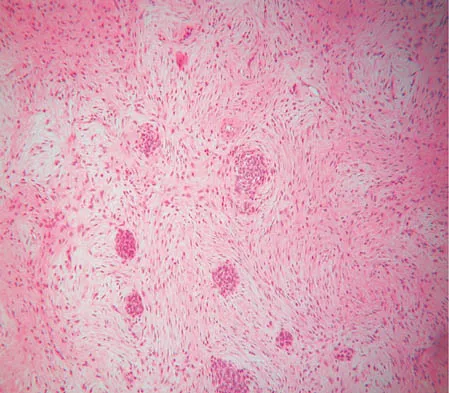

A 47-year-old woman has an asymptomatic pelvic mass that was discovered on routine gynecologic examination. A radiograph, CT scan, MRI scan, and biopsy specimen are shown in Figures 7a through 7d. Metastatic work-up is negative. Treatment should consist of

Explanation

The imaging studies show a chondrosarcoma; therefore, surgical treatment is indicated. There is no role for intralesional treatment of an exophytic lesion, particularly in the pelvis. Even obtaining a biopsy specimen risks intrapelvic contamination, although many surgeons would still perform a biopsy prior to a resection to confirm the diagnosis. Chondrosarcoma is considered resistant to both radiation therapy and chemotherapy; therefore, radiation therapy generally is not used except for unresectable lesions. Chemotherapy would be used only for metastatic disease or in patients with high-grade chondrosarcoma. The grade would not be known until after resection, and in this patient, the histology slide showed a grade I neoplasm. Chemotherapy would not be used preoperatively because a cartilage tumor is unlikely to shrink, and in this patient, the lesion is resectable. Springfield DS, Gebhardt MS, Mcguire MH: Chondrosarcoma: A review. J Bone Joint Surg Am 1996;78:141-149.